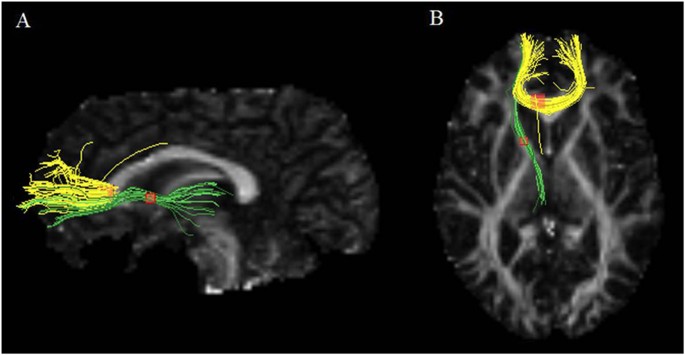

Coordinates for the AES-SDM analysis were obtained from all 18 datasets representing 641 patients with MDD and 581 HCS. As shown in Fig. 2 and Table 2, patients with MDD had significant FA reductions in 2 clusters relative to HCS. The largest cluster exhibited a peak in the genu of the corpus callosum (CC) extending to the body of the CC. The main tracts passing through this region were the interhemispheric fibres connecting the prefrontal and orbitofrontal cortices, shown as yellow tracts in Fig. 3. The other cluster exhibited FA reduction in the left ALIC. The main tracts passing through this region were the anterior thalamic radiation connecting the medial dorsal thalamic nuclei with the prefrontal cortices, shown as the green tracts in Fig. 3. No FA increases in any of the regions were reported in the analysis. The results from Egger’s test revealed no strong evidence for publication bias in the genu of the CC (P = 0.198) and left ALIC (P = 0.123).

Left image (A) observed from the left side of the brain, right image (B) observed from above. Tracts include the interhemispheric fibres running through the genu of the CC (yellow) and the anterior thalamic radiation running through the left ALIC (green). Sagittal and axial slices mapping the FA values are shown in the background for illustrative purposes. Abbreviations: CC, corpus callosum; ALIC, anterior limb of internal capsule; FA, fractional anisotropy.